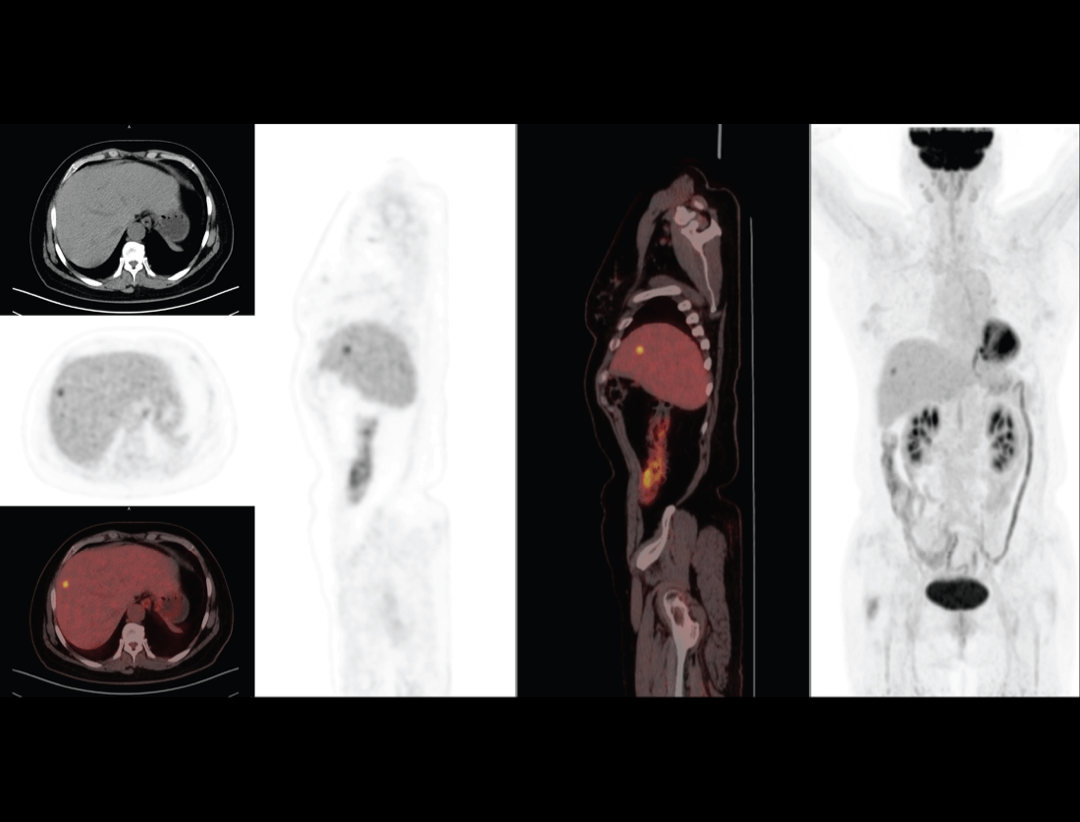

Integrated Oncology Application

The uMI 550 offers a comprehensive solution package for tumor diagnosis and post-therapeutic evaluation on the operation console.